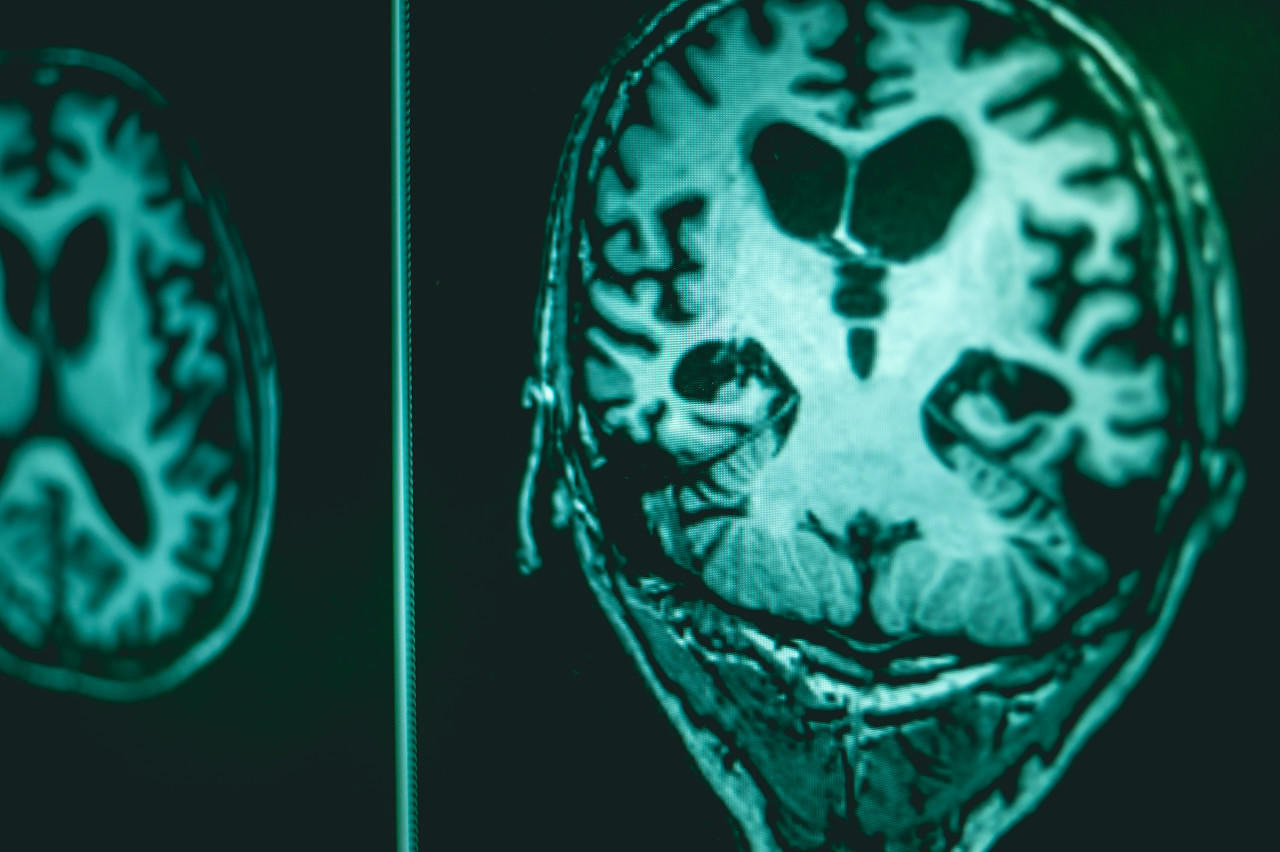

↑阿尔茨海默症患者还有可能出现激动、混乱甚至暴力狂躁等症状。资料图。

据了解,阿尔茨海默症会严重影响大脑,主要表现为认知功能下降、精神症状和行为障碍、日常生活能力的逐渐下降。随着时间推移,情况会愈发严重。专门研究刑事法庭案件的心理学家杰森介绍称,除了认知能力下降,患者还有可能出现激动、混乱甚至暴力狂躁等症状。不过他解释称,并不是所有患者都会出现上述症状,还是需要看具体情况。